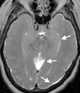

Carcinomatous infiltration

Leptomeningeal cancer (also called leptomeningeal carcinomatosis, leptomeningeal disease (LMD), leptomeningeal metastasis, neoplastic meningitis, meningeal metastasis and meningeal carcinomatosis) is a rare complication of cancer in which the disease spreads from the original tumor site to the meninges surrounding the brain and spinal cord. This leads to an inflammatory response, hence the alternative names neoplastic meningitis (NM), malignant meningitis, or carcinomatous meningitis. [Source: Wikipedia ]